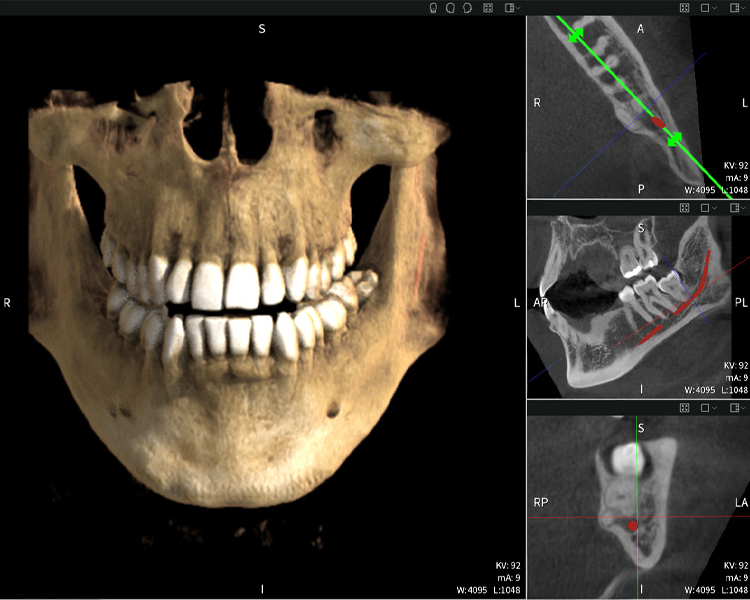

Figure d: Imaging results of Seethrough Max, in front of a black background.

Figure d

Figures b–d show various views of a 3D reconstruction of the mandible, providing a comprehensive overview of the mandibular anatomy, the position of the nerves in relation to the teeth, and allowing assessment of tooth symmetry and alignment.

Figure d shows the previously treated tooth 48, with its crown removed, and its roots left in proximity to the nerve, illustrating the high risk of nerve damage.